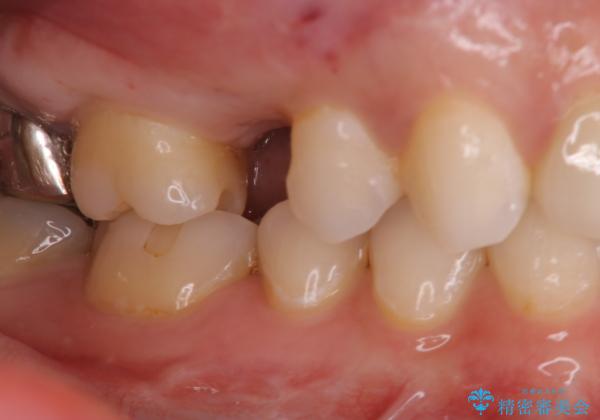

- 数年前に他医院で抜歯したままで過ごし、今回歯を入れたいとのことで来院された患者様です。

治療回数を短くしたいと1DAYインプラントを希望されました。

インプラント埋入手術は1回で全て行い、2ヶ月後にはセラミック治療で、審美回復と機能回復をしました。